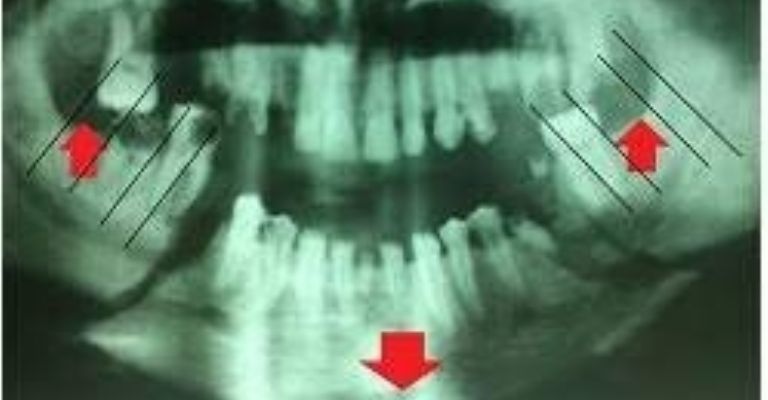

El caso ocurrió en febrero pasado, cuando el culpable le propinó dos golpes de puño en el rostro a su pareja provocándole una grave fractura de su mandíbula con deformación de rostro, tal como lo muestra la radiografía practicada a la víctima y que fue expuesta durante el juicio.